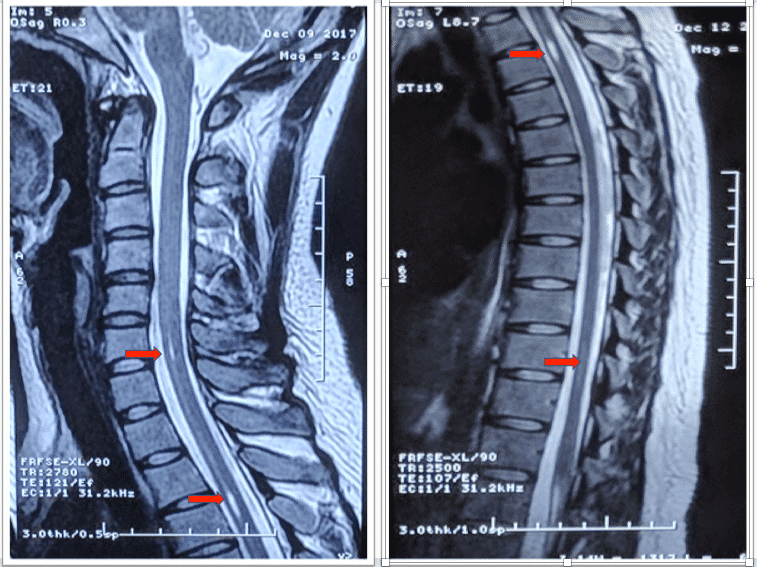

一、病例特点患者青年女性,21y,慢性病程;临床表现为颈背部疼痛,双上肢无力伴感觉障碍;既往有肠易激综合征病史9年,痔疮病史6月;查体:神清语利,认知功能正常;颅神经功能正常;双上肢近端肌力5级,远端4-级,肱二头肌、肱三头肌、桡骨骨膜及膝腱反射(+++),双侧Babinski Sign(-)。辅助检查:颈髓+增强:C6、T2-T3水平髓内多发异常信号;头MRI未见明显异常。二、神经影像颈髓&胸髓MRI+增强(2018-1-15首都医科大学宣武医院):颈椎曲度变直;C2-6椎体水平龍内异常信号影,考虑轻度中央管扩张;T3椎体水平信号异常,考虑中央管扩张可能。三、临床印象脊髓空洞症Tips 心情驿站